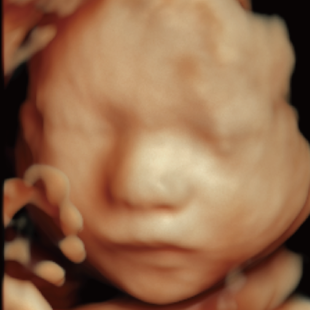

Voluson Expert 22®(GEHealthcare)という産婦人科領域におけるハイエンド超音波診断装置を使用しています。 従来機種と比べ、より高精細な画像描出性能と高度な解析機能を備えており、 胎児の発育や形態をより詳細に観察することが可能です。

通常の妊婦健診で行う超音波検査では、主に胎児発育(推定体重)、羊水の量、胎児の向きを確認しています。一方で健診の限られた時間内では、胎児を詳細かつ系統的に評価することが難しい場合があります。当院で行っている胎児超音波スクリーニングとは、高性能な超音波検査機器を用いて胎児の発育や形態(からだの構造)をより詳しく観察し、胎児の状態を丁寧に評価する検査です。 出産前に赤ちゃんの状態をより詳しく知りたいという患者さんのご希望にお応えするため、当院では超音波検査士*および超音波専門医・指導医**が胎児超音波スクリーニングを担当します。